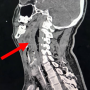

Initial computed tomograpgy neck showed extensive multiloculated gas containing collection seen at retropharyngeal region (red arrow) from the level of oropharynx in sagittal section

Case Report Page 551 - 556

Retropharyngeal Abscess with a Missed Migrating Foreign Body: A Case Report